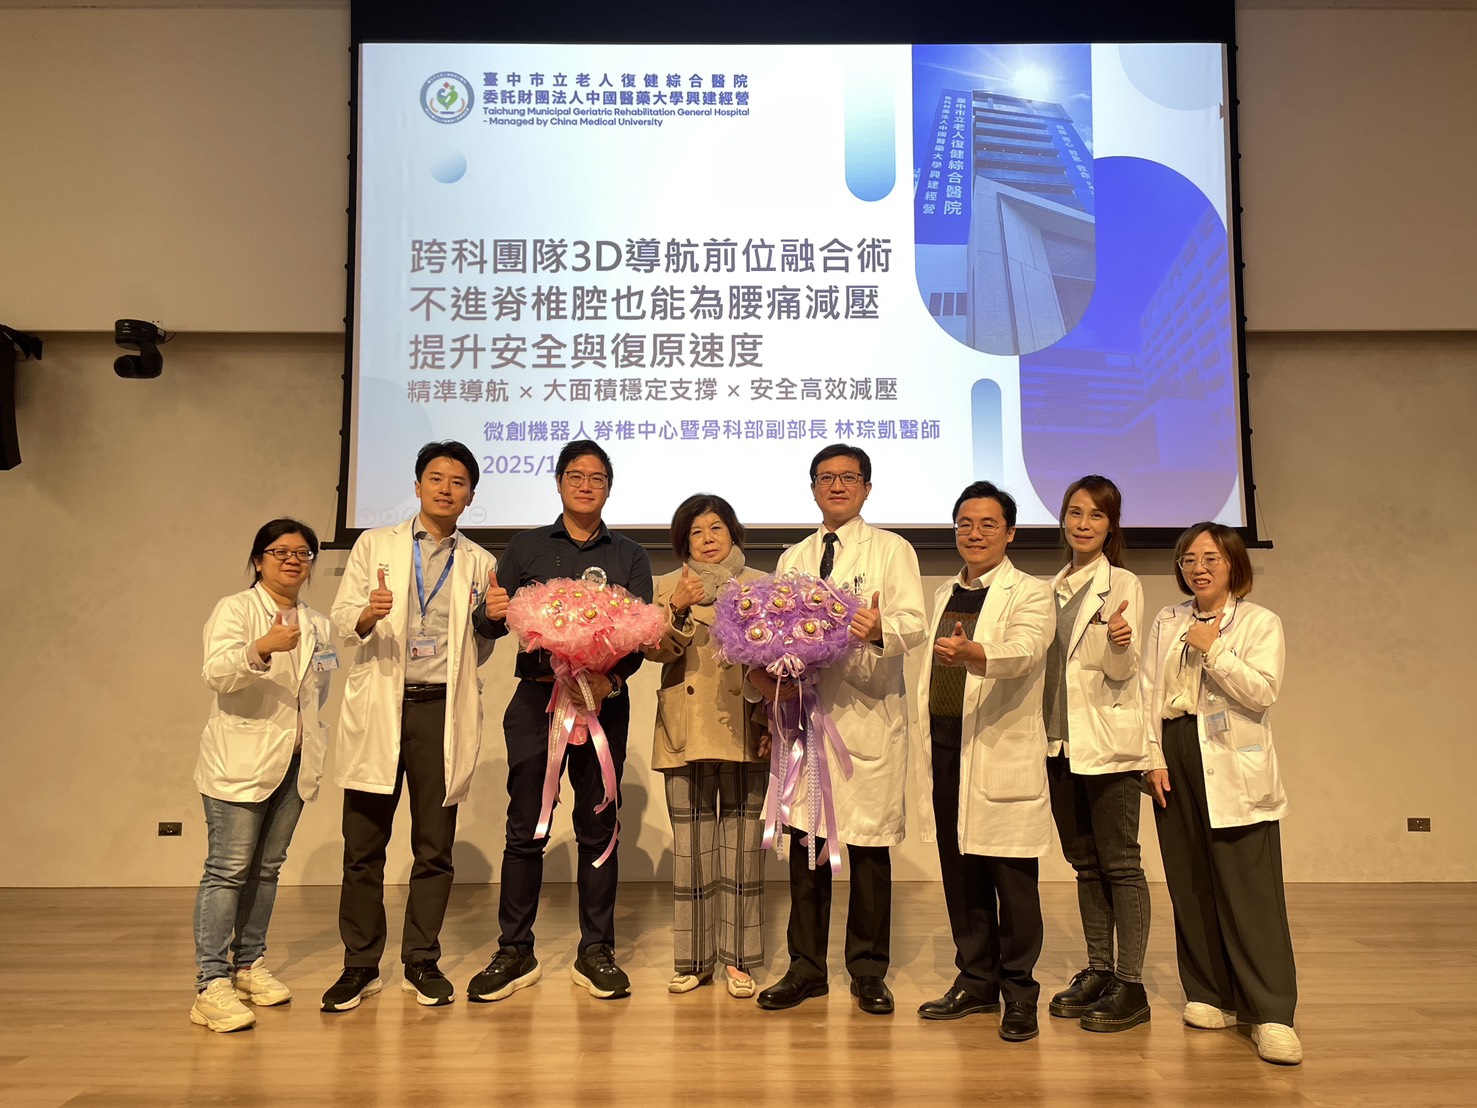

患者術後神經症狀明顯改善,特別獻花感謝骨科副部長林琮凱醫師。官方提供

患者與本院微創機器人脊椎中心團隊合影,脊椎中心助理副院長張建鈞醫師(右三)、骨科副部長林琮凱醫師(右四)與骨科醫護人員。官方提供